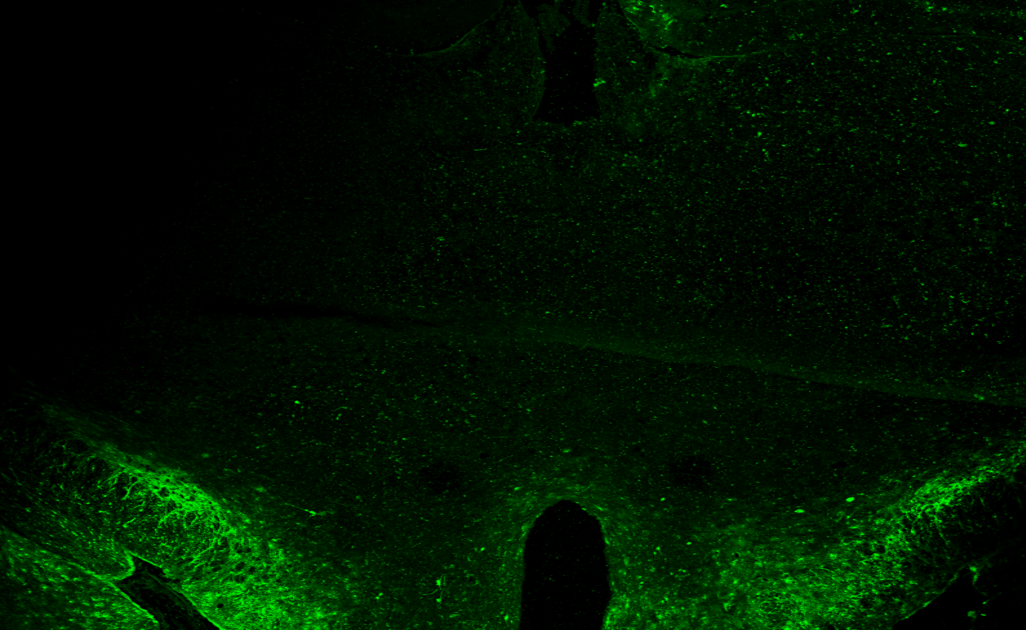

Le projet THALATEL, dirigé par Vincent Géli, vise à explorer le rôle de la télomérase dans la sénescence cellulaire. Cette enzyme, censée protéger nos chromosomes, se révèle être un acteur clé dans la régulation de notre appétit. En testant des souris génétiquement modifiées, les chercheurs ont constaté une préservation de leur santé cellulaire, mais à quel prix ? En vieillissant, ces souris développent une faim insatiable, mettant en lumière un lien troublant entre longévité et obésité.

La recherche démontre que la télomérase, loin d’être un simple réparateur de chromosomes, agit également comme un régulateur métabolique. En perturbant son expression dans l’hypothalamus, les souris montrent une prise de poids rapide, révélant ainsi une interconnexion entre le cerveau et le métabolisme. Ce constat pourrait faire trembler les fondations des politiques de santé publique qui prônent la lutte contre l’obésité sans tenir compte des mécanismes biologiques sous-jacents.